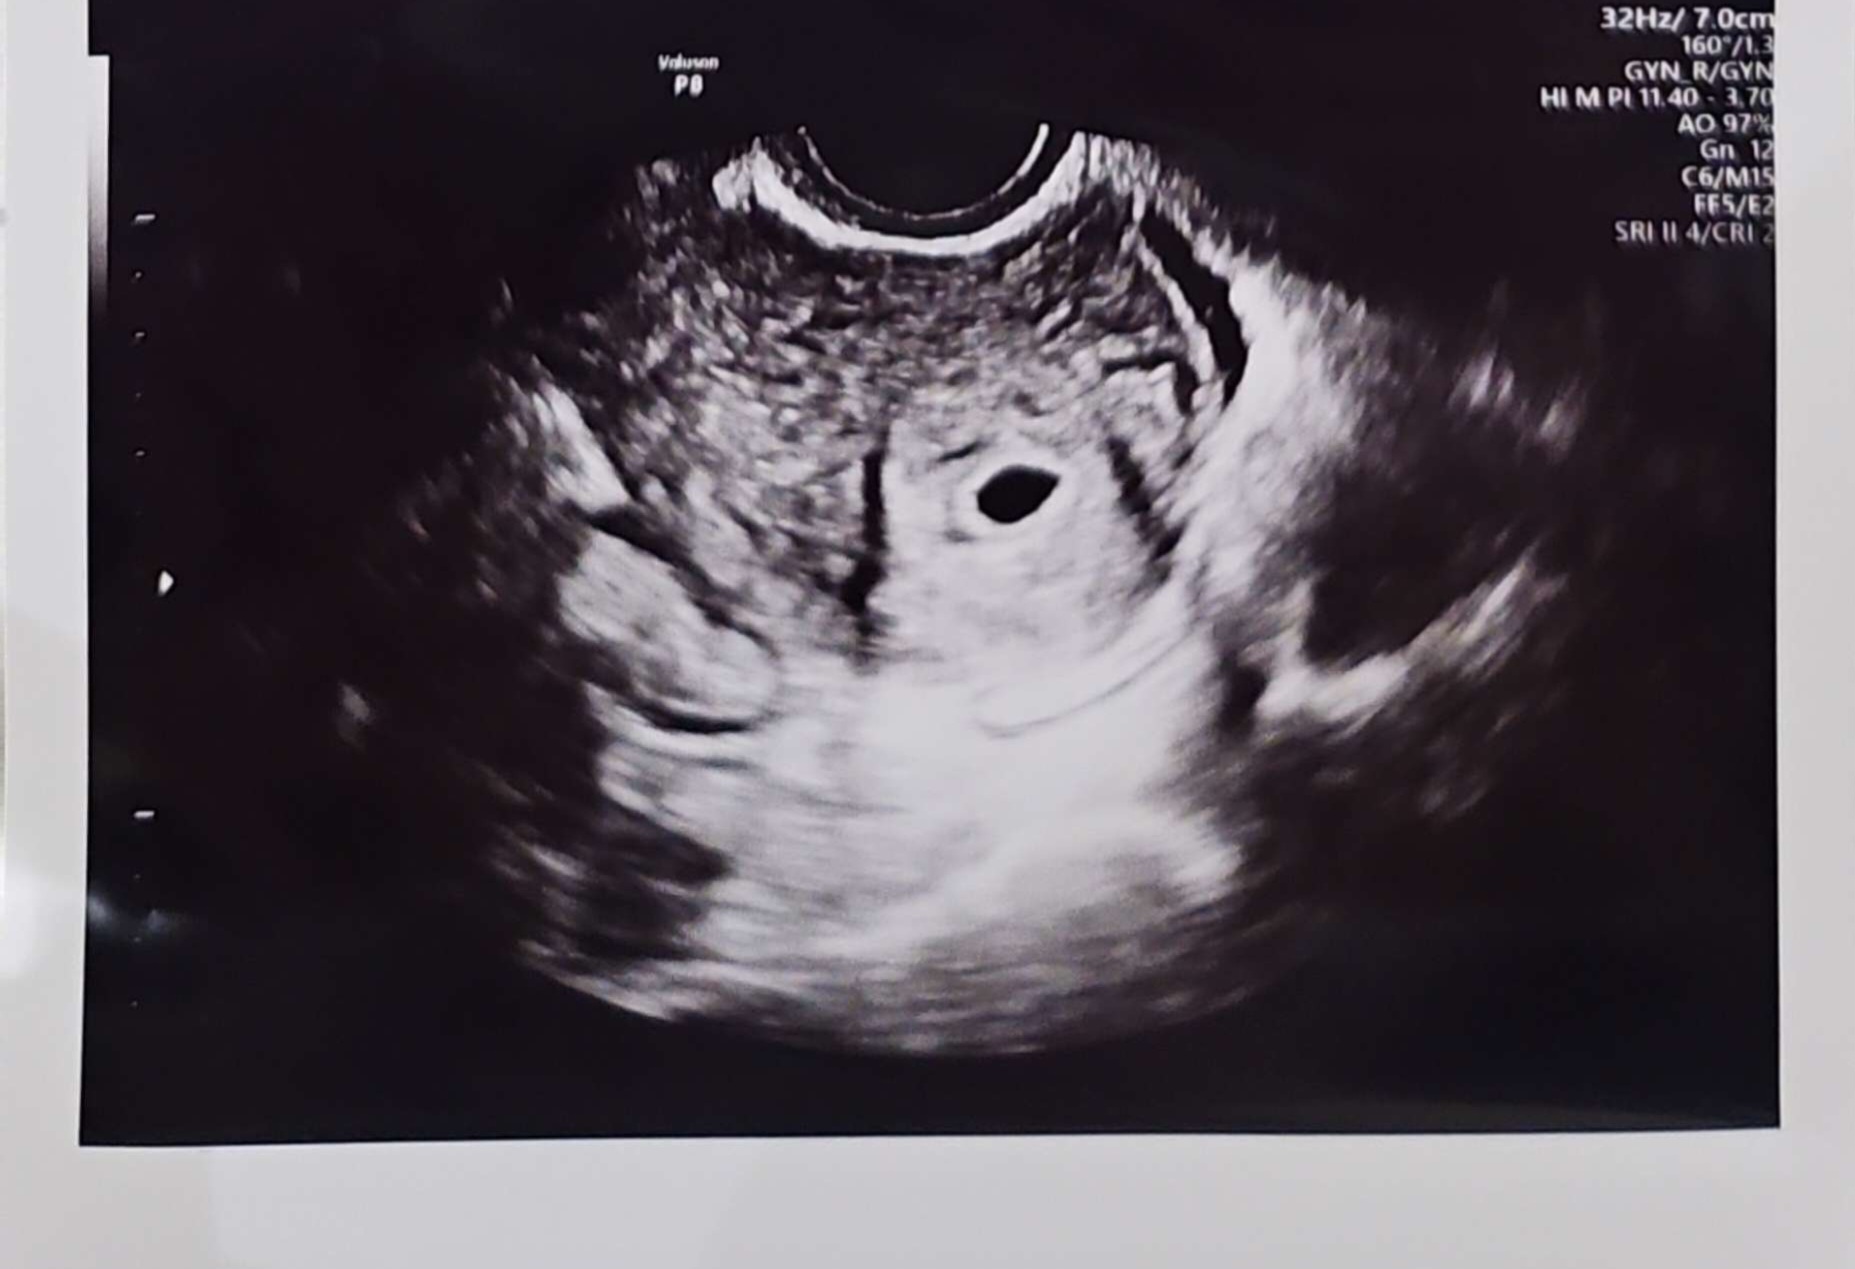

올 초에 임신 했었는데 딱 이 맘 때쯤 아기집만 보고 심장 소리는 못 듣고 유산했던 맘입니다... 5주 4일차의 초음파인데 왜 난황도 안 보일까요 ㅜ.ㅜ 좀 늦는건 아닐지... 초조합니다

저도 5주3일 난황안보였어요ㅜ 불안해서 오늘 딱6주라 쓰리라인테스트기 해보니 1번이 진하게 역전했어요ㅎㅎ 더 튼튼하게 크려고 조금 늦나봐요